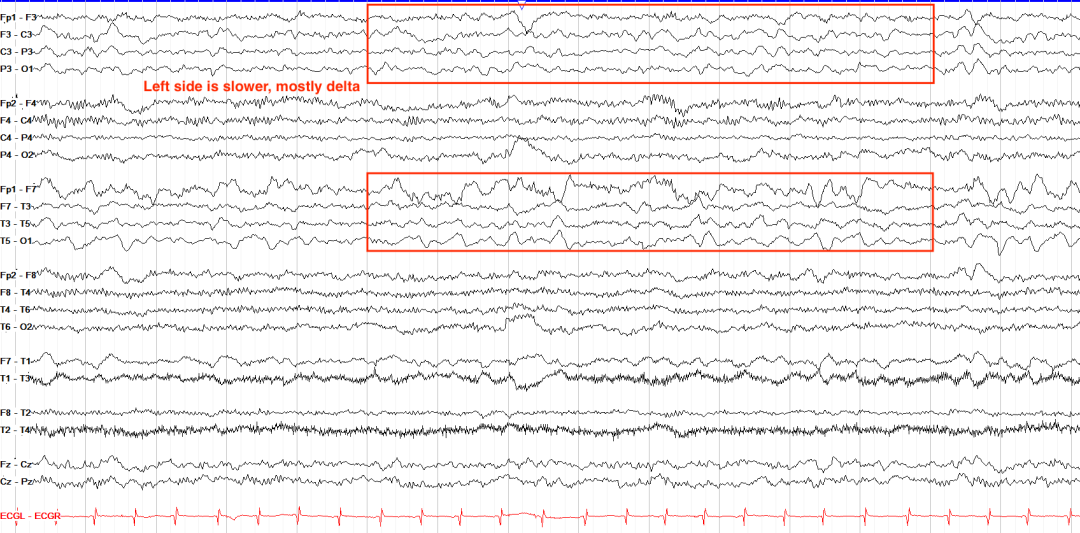

在对称性中,左右两侧在幅度和频率方面基本相同。健康的脑电图应该始终是对称的,间歇性或持续性的不对称可能由肿瘤或出血等结构性实体引起。对称性的变化可能很微妙,下面不对称的例子中,左半球的幅度更高,与右侧相比具有更慢的δ活动。

•局灶性慢波:θ/δ波持续出现于特定脑区,提示结构性病变(如肿瘤、梗死)。